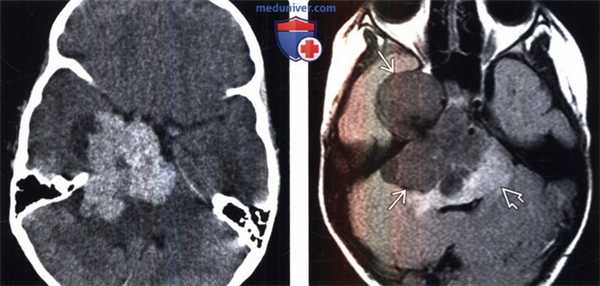

(Слева) Бесконтрастная КТ, аксиальный срез: определяется дольчатое гиперденсное объемное образование, расположенное по ходу намета мозжечка справа.

(Справа) МРТ, FLAIR, аксиальный срез: у этого же пациента визуализируется гипоинтенсивное многодольчатое объемное образование с перифокальным отеком и масс-эффектом на IV желудочек.

2. КТ признаки атипичной и злокачественной менингиомы:

• Бесконтрастная КТ:

о Триада ММ при КТ: внечерепное объемное образование, остеолизис, внутричерепная опухоль

о Гиперденсное образование; кальцификация минимальна или отсутствует:

- Кальцификация= обычно более низкий темп роста

о Выраженный перифокальный отек, деструкция кости